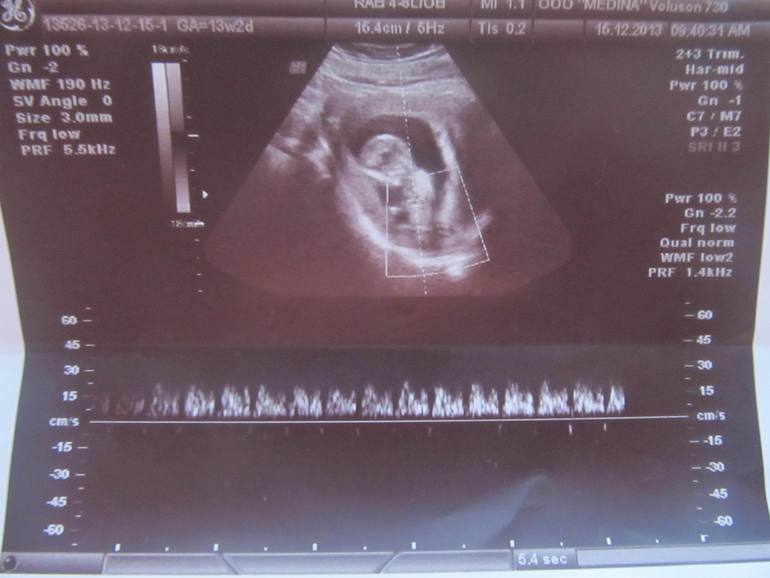

1 скрининг(УЗИ) и фото малышастика

Результаты: УЗИ, КТГ, доплера, скринингаСегодня была на 1 скрининге.

сказала,что всё хорошо у нас , по показателям соответствуем сроку 13нед и

2 дня. Единственное, ей не понравилось,что плацента низковата расположена,сказала не перетруждаться и не поднимать тяжестей.

ПДР поставила на 20.06.2014(хотя по моим подсчетам срок на неделю меньше,ну да ладно). Сразу после УЗИ в лаборатории взяли кровь,результат крови будет в среду,теперь дожить бы до среды,надеюсь результат придет хороший!

В заключении написала миома матки,миома опять увеличилась,врач сказала не расстраивайся,матка питается сейчас,вот и миома растет,всё будет хорошо,таких случаев кто рожают с миомой много.